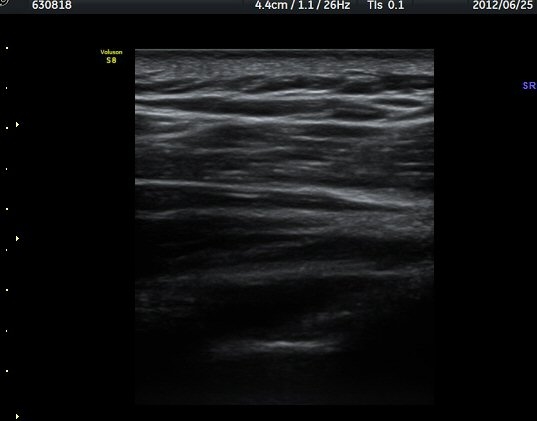

¾î±ú °üÀý µÚÂÊ ÈĹæ°üÀý¼ø Ⱦ´Ü¸é°Ë»ç¿¡¼­ °üÀý¼ø ³»Ãø, °¡½Ãµ¹±â°üÀý¼ø°í¶û(spinoglenoid

notch)¿¡¼­ Àú¿¡ÄÚ ³¶Á¾ÀÌ °üÂûµÈ´Ù(±×¸² 1). ŽÃËÀÚ¸¦ À§-¾Æ·¡ ¹æÇâÀ¸·Î º¯°æÇÏ¿© °üÂûÇÒ ¶§µµ

¿ª½Ã °ß°©°ñ °¡½Ãµ¹±â(spine) ¾Æ·¡¿¡¼­ Àú¿¡ÄÚ ³¶Á¾ÀÌ °üÂûµÈ´Ù(±×¸² 2). º¼·ÏŽÃËÀÚ·Î ¹Ù²Ù¾î °ü

ÂûÇÏ´Ï  °¡½Ãµ¹±â°üÀý¼ø°í¶û¿¡¼­ Àú¿¡ÄÚ ³¶Á¾ÀÌ ´õ¿í ¶Ñ·ÈÈ÷ °üÂûµÈ´Ù(±×¸² 3, 4).